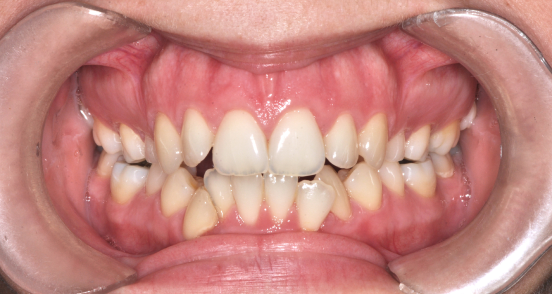

Előtte fogsor - Ínymosoly műtéti megoldása​

Utána fogsor - Ínymosoly műtéti megoldása​

Az ínymosoly ebben az esetben nem pusztán esztétikai kérdés volt.

A felső állcsont függőleges túlnövekedése és az alsó állkapocs helyzete együtt bontotta meg az arányokat.

A kezelést fogszabályozással készítettük elő, majd kétállcsontos állcsontműtétet végeztünk.

A felső állcsont pozíciójának módosításával csökkent az ínyláthatóság,

az alsó állkapocs korrekciója pedig stabil harapást eredményezett.

Eredmény: kevesebb íny, harmonikusabb arcprofil, hosszú távon stabil funkció..